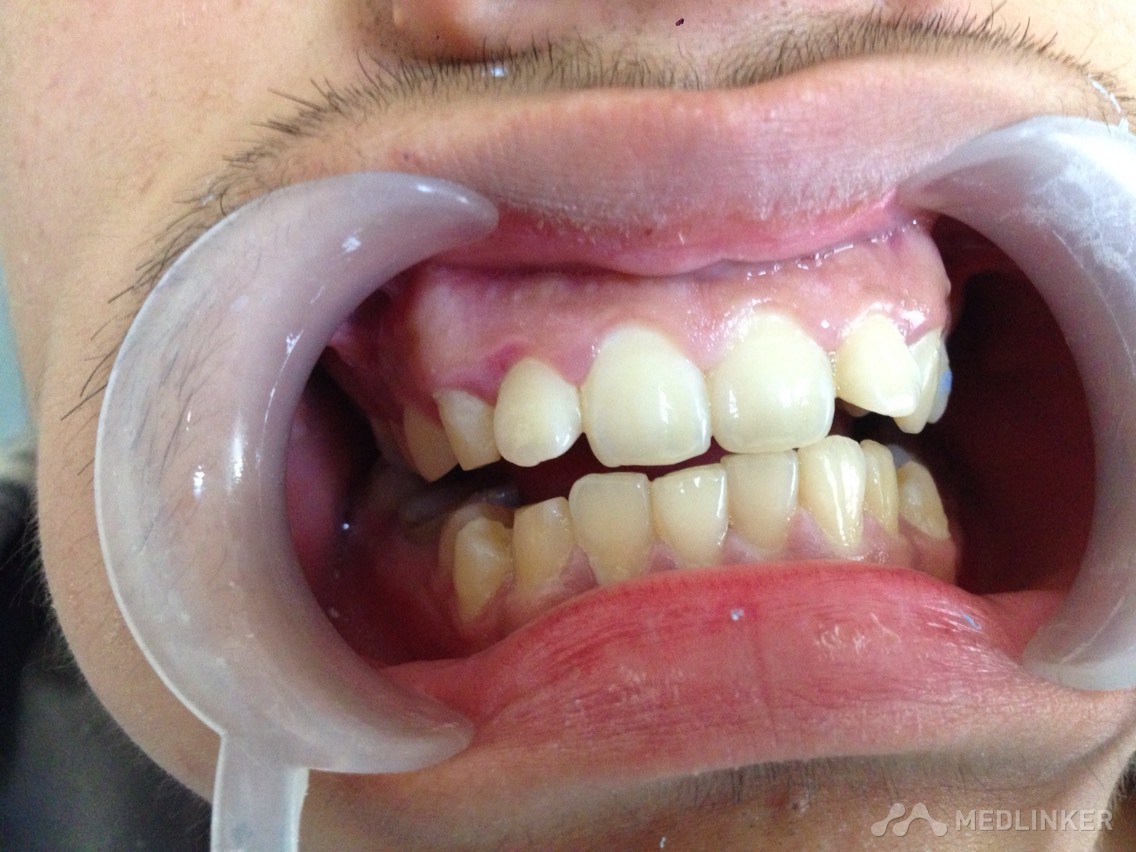

患者男,17岁,上前牙不美观要求矫正

各位同仁帮忙看下这个患者适合怎么矫正?

各位同仁帮忙矫正的方案是怎么样?